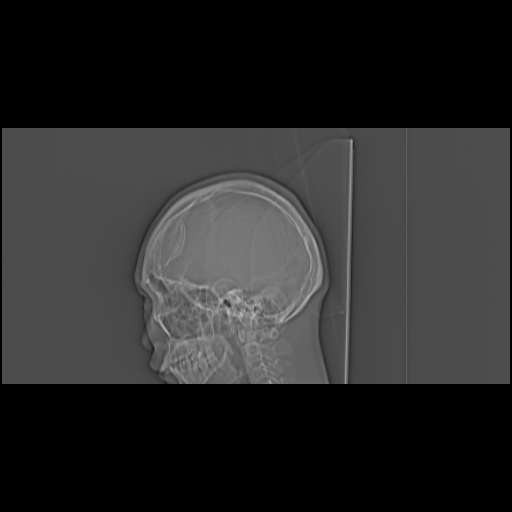

标题: CT21939:男20岁,外伤一年后,现头疼. [打印本页]

标题: CT21939:男20岁,外伤一年后,现头疼.

左侧额部硬膜外血肿机化、骨化。

左侧额部硬膜外血肿机化、骨化